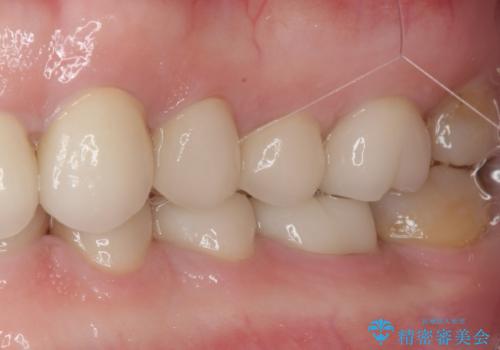

口を開けたときに見える範囲をオールセラミッククラウンとし、とても自然な口元に仕上げることができました。